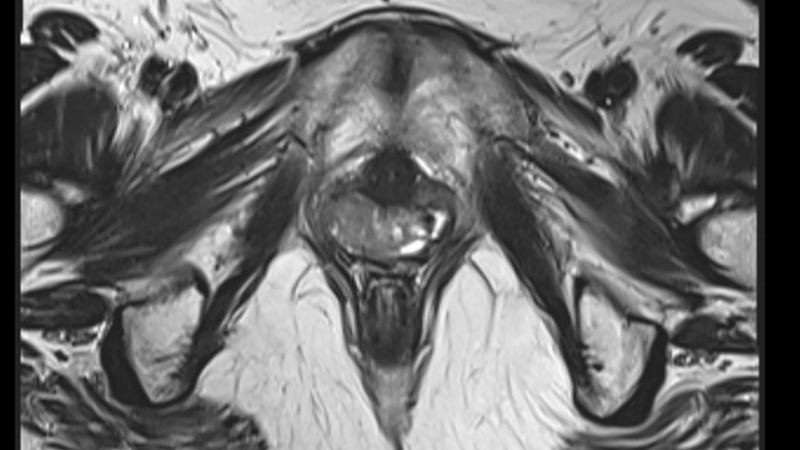

Algunas pruebas de imagen ayudan a diagnosticar el síndrome

Como los genitales externos son normales, hay más dificultad para diagnosticar el síndrome. Los médicos suelen notar algo "anormal" durante la consulta y ordenan pruebas ginecológicas.

"Podemos pedir un examen pélvico, una ecografía y también una prueba genética para verificar si la paciente tiene los cromosomas XX", explica Claudia Takano, coordinadora del ambulatorio de malformaciones genitales de la Universidad Federal de São Paulo (Unifesp), el único que trata el síndrome por el Sistema Único de Salud, público y gratuito en Brasil.